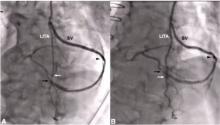

Can a Single ITA Composite Graft Adequately Supply the Heart? [3]

Marc Ruel